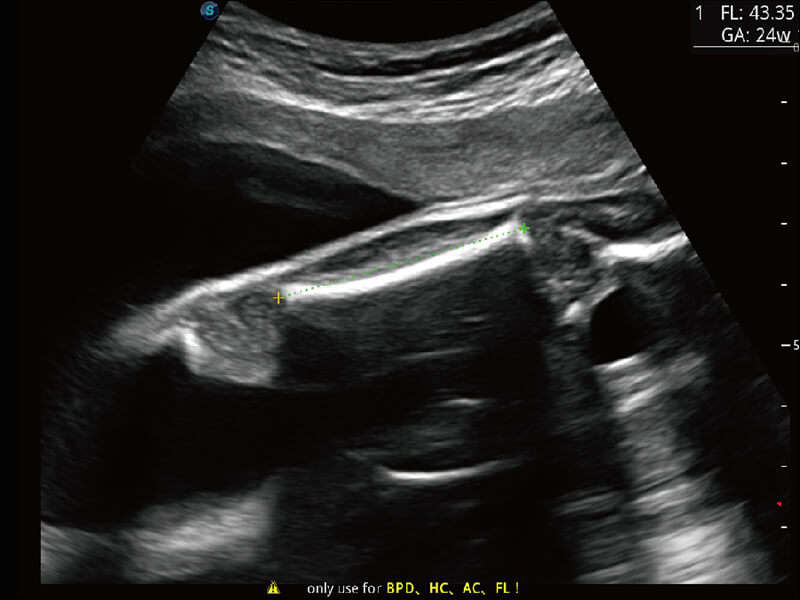

S-Fetus 产科扫查助手

• 缩短

操作时间

• 提升

准确率

• 单次

按键操作

高分辨率容积成像 栩栩如生

超宽频带技术,为容积成像带来优质的二维图像基础,为您呈现丰富的结构细节,栩栩如生地展示宝宝的宫内形态以及各种组织的立体结构。